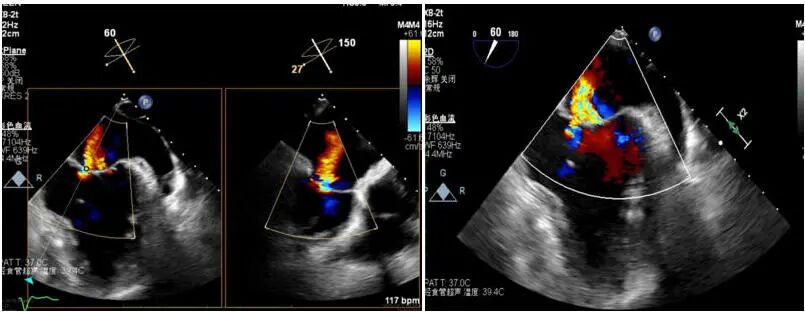

患者女性,72岁,反复心悸、胸闷多年,既往曾在外院接受房颤射频消融,但术后再次复发。入院后检查发现:房颤合并中重度二尖瓣反流,且瓣口面积仅4.3cm²,病情复杂、风险极高。经多学科团队联合评估,本次手术中,团队通过三维标测系统精准定位心律失常触发点,并以脉冲消融完成心房电活动重构。消融后心律即刻恢复窦性节律,体现了PFA在病例中快速、精准、微创的独特优势。与传统射频消融相比,脉冲消融显著减少肺静脉狭窄及食管损伤风险,术后房颤复发率更低,为房颤患者提供了更优的治疗方案。针对患者的中重度二尖瓣反流,手术团队在精准经食道超声导航下完成TEER瓣膜修复。瓣叶精准对合后,反流明显减少,跨瓣压差维持在理想水平,术后心功能显著改善。

术前患者二尖瓣反流中重度,二尖瓣后叶栓系,反流主要集中在2区,累及部分1区和3区,瓣口面积仅有4.3cm²

在瓣口面积偏小仅有4.3cm²的情况下,决定术中在2区植入一枚SW0609型号DragonFly™二尖瓣夹解决反流问题,术中用到DragonFly™二尖瓣夹前后瓣叶独立捕获功能,实现了对病变瓣叶的精准定位与捕获。术中房间隔穿刺高度3.8cm,夹闭后L侧微量反流,释放后反流未明显增加,跨瓣压差2mmHg